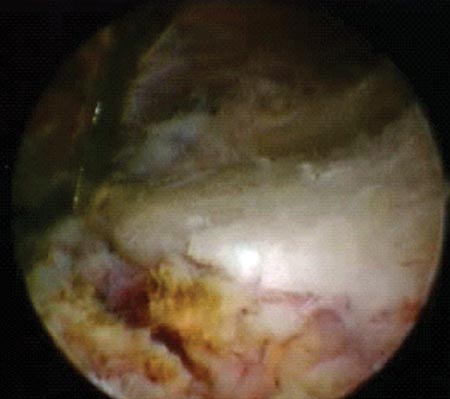

Figura 1C: Espacio subacromial. Reducción artroscópica fractura del troquíter. Se observa línea de fractura./ Figura 1D: Osteosíntesis artroscópica con tornillos canulados de 3.5 mm./ Figura 1E: Reducción y ostesíntesis con 3 tornillos canulados de 3.5 mm. Flecha: pérdida de hueso. Reparación de Bankart y SLAP asociada.

A través de la visualización artroscópica posterolateral y bajo asistencia simultánea por radioscopia con proyecciones de frente y axial, se intenta la reducción de los fragmentos óseos. La reducción de los fragmentos óseos se realiza con el gancho palpador desde cualquiera de los portales anteriores previamente realizados o a través de los portales laterales. En la mayoría de los casos mediante la utilización de la rotación externa o interna del miembro y la confección de uno o dos portales laterales, es suficiente para alcanzar un manejo aceptable de la reducción de los fragmentos óseos y finalmente de la osteosíntesis. La visualización principal durante el proceso de reducción y osteosíntesis de los fragmentos se realiza fundamentalmente a través del portal postero lateral semejante a la reparación del manguito rotador.